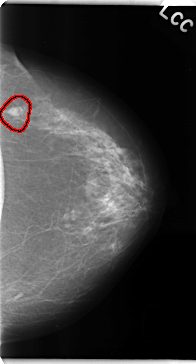

C_0135_1.LEFT_CC

LEFT_CC LINES 4728 PIXELS_PER_LINE 2544 BITS_PER_PIXEL 12 RESOLUTION 50 OVERLAY

FILE: C_0135_1.LEFT_CC.OVERLAY

TOTAL_ABNORMALITIES 1

ABNORMALITY 1

LESION_TYPE MASS SHAPE OVAL MARGINS MICROLOBULATED

ASSESSMENT 4

SUBTLETY 5

PATHOLOGY MALIGNANT

TOTAL_OUTLINES 1

BOUNDARY